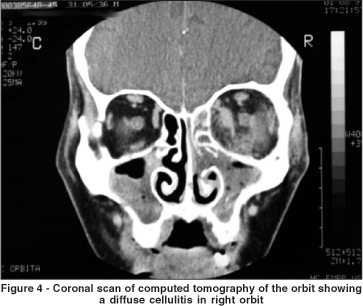

In order to categorize the radiological patterns of cellulitis the following guidelines were adopted. Diffuse fat infiltration was characterized by an increased density of the extra- or intraconal fat. The limits of the transition between the normal fat and the enhanced fat density were typically gradual and not well defined. A subperiosteal abscess was diagnosed when the periorbita was elevated from at least one orbital wall adjacent to a paranasal sinus. Finally, an orbital abscess was defined whenever an abnormal heterogeneous density was found (with or without ring appearance) within the orbital fat.

In all cases intraorbital changes could be detected. Diffuse infiltration was seen as an isolated feature in 11 patients (24.44%) who were successfully managed using medical treatment with intravenous antibiotics alone (Figure 4). As shown in Figure 5, subperiosteal abscesses were diagnosed in 28 patients (62.23%). The detached periosteum was usually well demarcated, defining the border of fluid collection. In 9 patients (20%) there was a diffuse fat infiltration at the boundaries of periorbita elevation (Figure 6). Orbital abscesses were seen in 6 patients (13.33%, Figure 7). All of these cases were surgically confirmed.